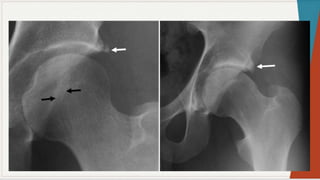

Radiografia Simples:

◗ Incidência ântero-posterior:

observar

as

características: espaços

articulares e

linhas

seguint

es

pélvica

s,

presença de qualquer doença óssea, ângulo colo-

diafisário, forma da cabeça femoral, presença de

osteófitos, evidência de fratura ou luxação,

evidência de deformação pélvica.

Radiografia Simples: ◗ Incidênciaântero-posterior: observar as características: espaços articulares e linhas seguint es pélvica s, presença de qualquer doença óssea, ângulo colo- diafisário, forma da cabeça femoral, presença de osteófitos, evidência de fratura ou luxação, evidência de deformação pélvica.